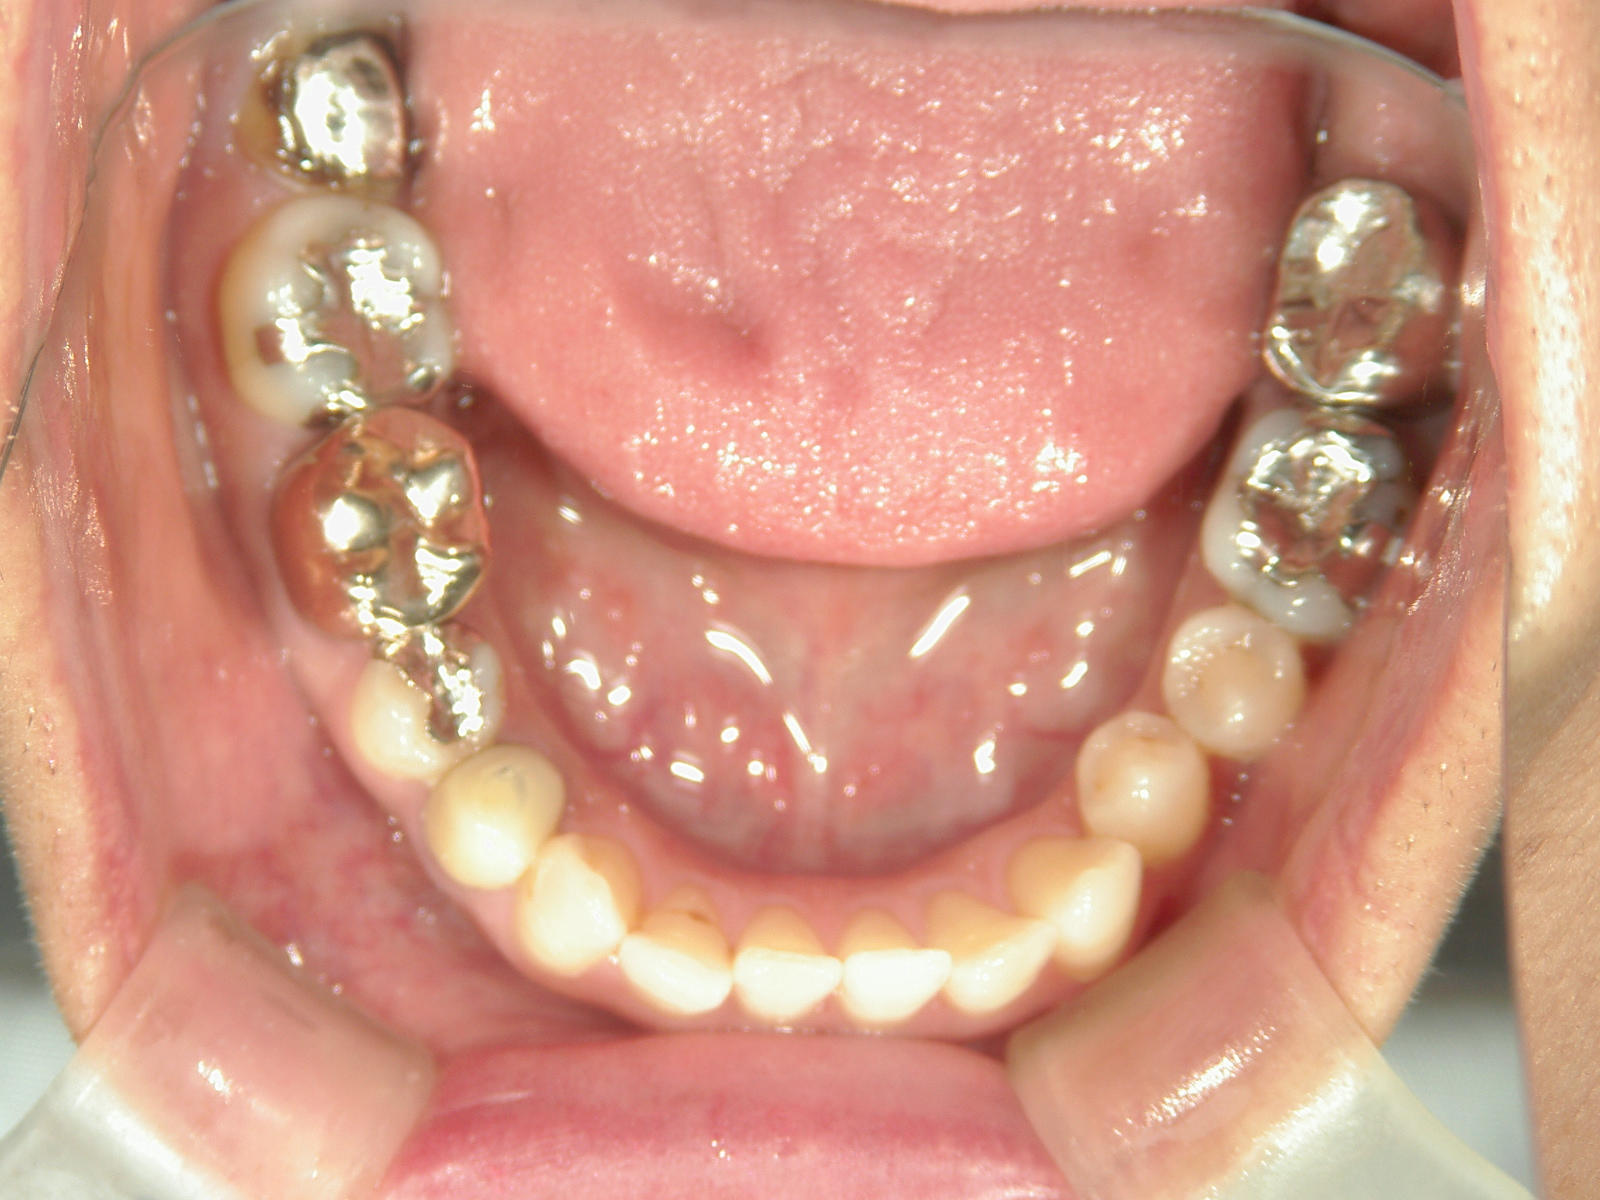

右下第一小臼歯(1本)、右下親不知(1本)を抜歯。

右下第一大臼歯をセラミックへ変更。

上顎骨切断OPE、矯正装置(MSE+フェイスマスク)、ワイヤー矯正を併用。

①患者様はインビザライン矯正をご希望でしたが、上顎骨が小さく、受け口になっているので、インビザライン矯正で治療するために「骨切断OPE」「矯正装置(MSE+フェイスマスク)」で上顎骨を拡大しました。